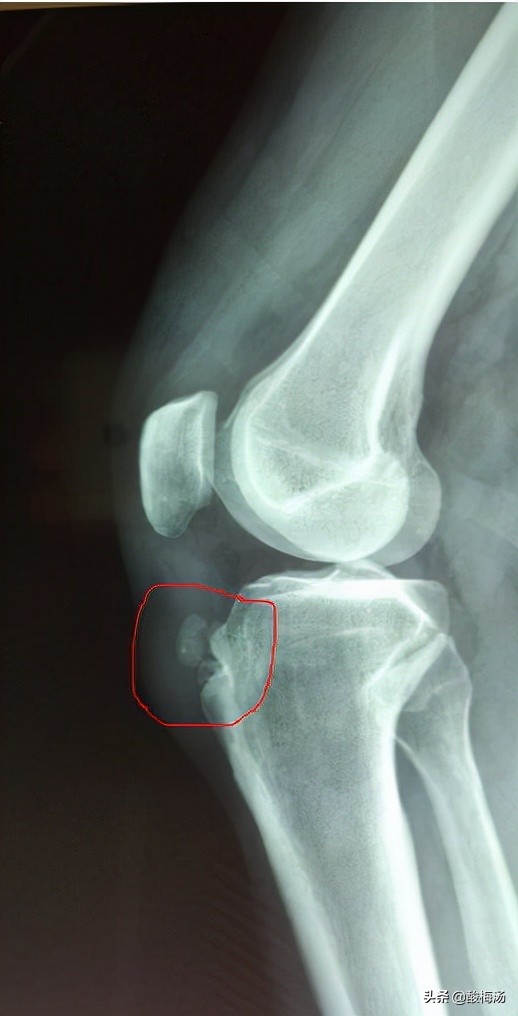

胫骨结节骨骺炎,又称胫骨结节骨软骨病,胫骨结节骨软骨炎,胫骨结节骨骺无菌性坏死。好发于青春发育期,11~15岁的男孩,多为发育加快,喜好运动者,可有剧烈运动或外伤史。胫骨结节处疼痛,活动后加重。胫骨结节局部可有肿胀,压痛,甚至红热。主动伸膝,被动屈膝或蹲起时加重,是髌腱牵拉骨骺所致。在青春发育期,股四头肌肌腱的自身发育,导致张力增加,导致胫骨结节骨骺局部炎症、肿胀,当运动时,膝关节处于屈曲位置时,股四头肌肌腱张力最大,牵拉胫骨结节骨骺,长期、反复的牵拉,对胫骨结节骨骺肯定造成进一步的损伤,慢性损伤导致进一步的缺血坏死,从而引起临床症状。这就是胫骨结节骨骺炎的发病机制。拍片时可看到胫骨结节处骨骺隆起,其间骨化不均匀,可有翘起骨片或游离骨片。